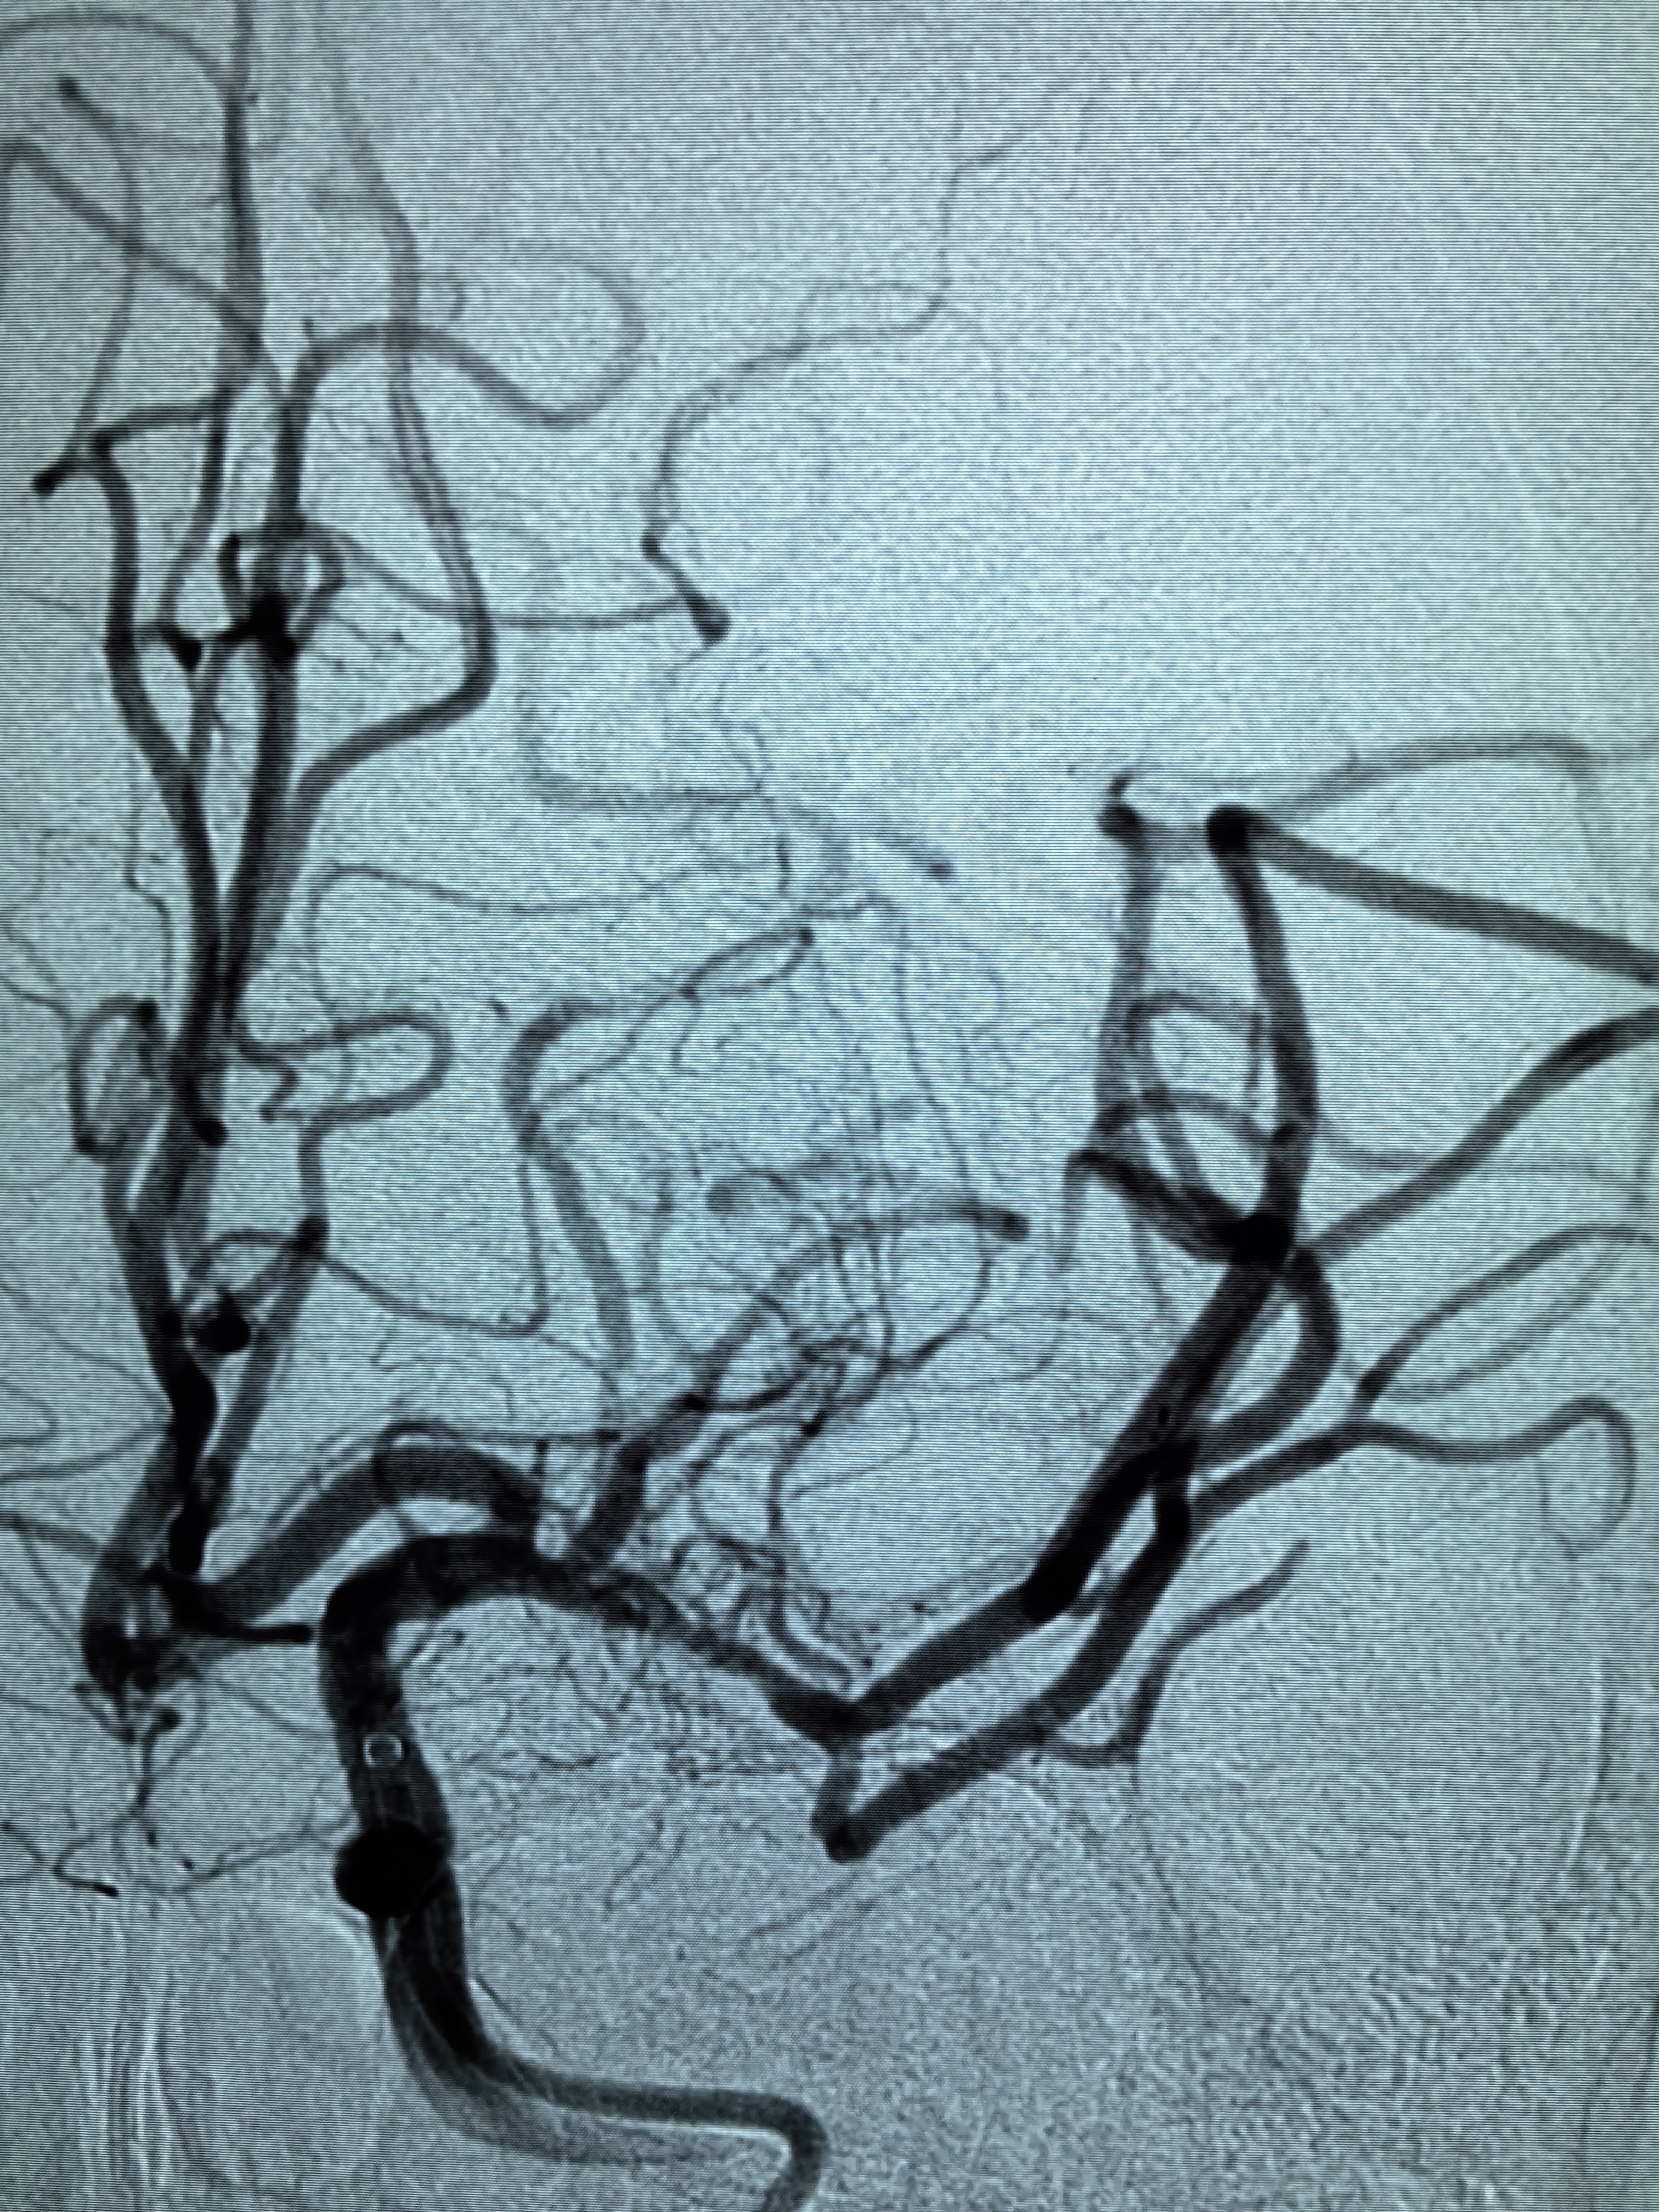

1、本例患者老年女性,系骨科术后次日醒后卒中,经核磁评估提示左侧大脑中动脉闭塞,系责任血管,患者心电图示房颤,考虑心源性栓塞可能性大。

2、本例患者SWIM技术取栓一次后血管再通,颅内血流通畅。